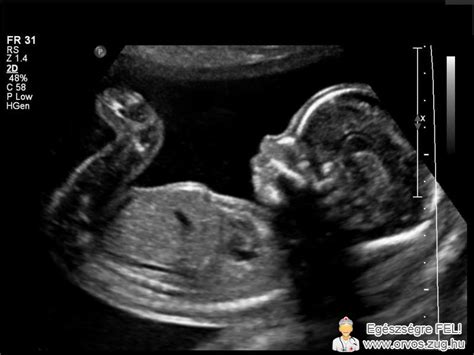

A diagnózis ultrahangvizsgálattal, méhtükrözéssel (hiszteroszkópia), hysterosalpingográfiával (HSG) vagy laparoszkópiával történhet. A HSG során kontrasztanyagot juttatnak a méh üregébe, amely kirajzolja a méhűr alakját.

A kettős méh jelentősen megnehezítheti a teherbeesést és a terhesség kihordását. A spermiumoknak kétfelé kell oszlaniuk, így kevesebb jut el a petesejthez. A méh mérete is kisebb lehet, ami korlátozhatja a magzat fejlődését és növekedését.

- Helyszűke: A magzatnak kevesebb helye van mozogni, ami befolyásolhatja fejlődését.